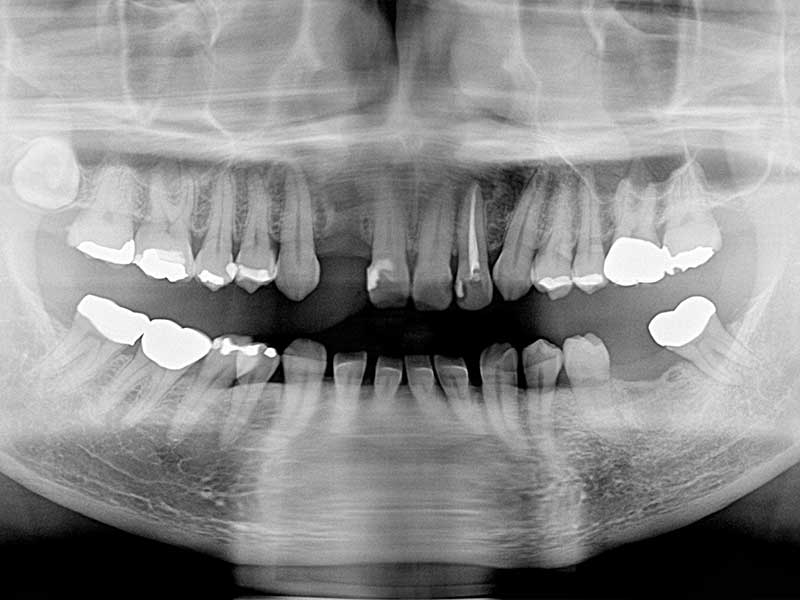

術前(レントゲン写真)

術後(レントゲン写真)